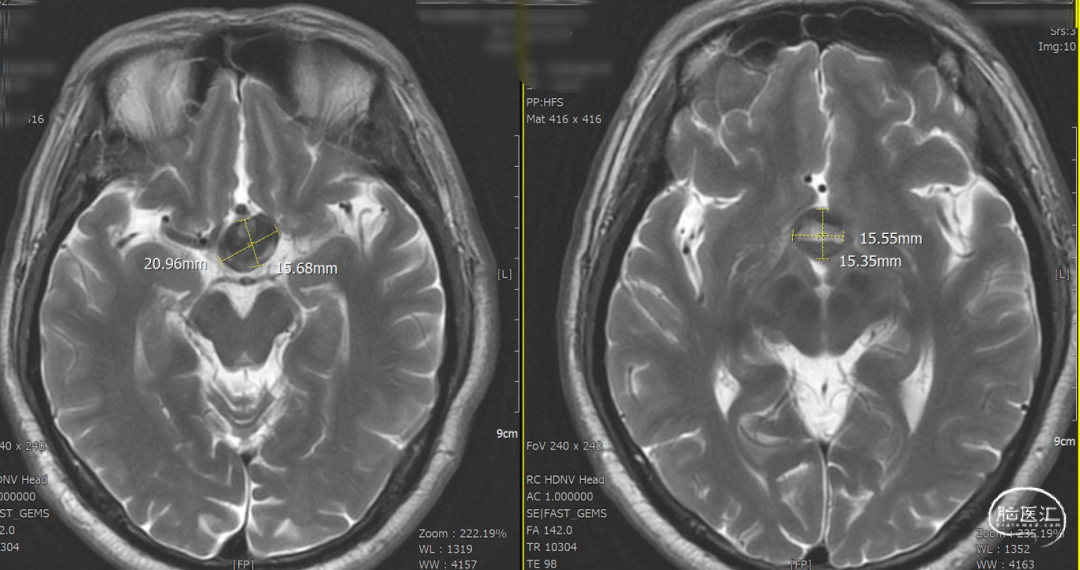

辅助检查示:2025-01-08 鞍区及垂体MR平扫:鞍内及鞍上肿瘤,垂体瘤并卒中?建议鞍区及垂体MR增强扫描。

DSA造影3D重建测量